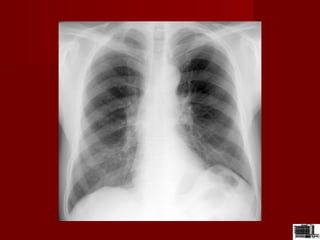

Radiografia toracicaRadiografia toracica

 Opacitatea centrala a toracelui este compusaOpacitatea centrala a toracelui este compusa

din inima,aorta ,hiluri ,arteredin inima,aorta ,hiluri ,artere

pulmonare,trahee,bifurcatia in cele 2 bronsiipulmonare,trahee,bifurcatia in cele 2 bronsii

principale.principale.